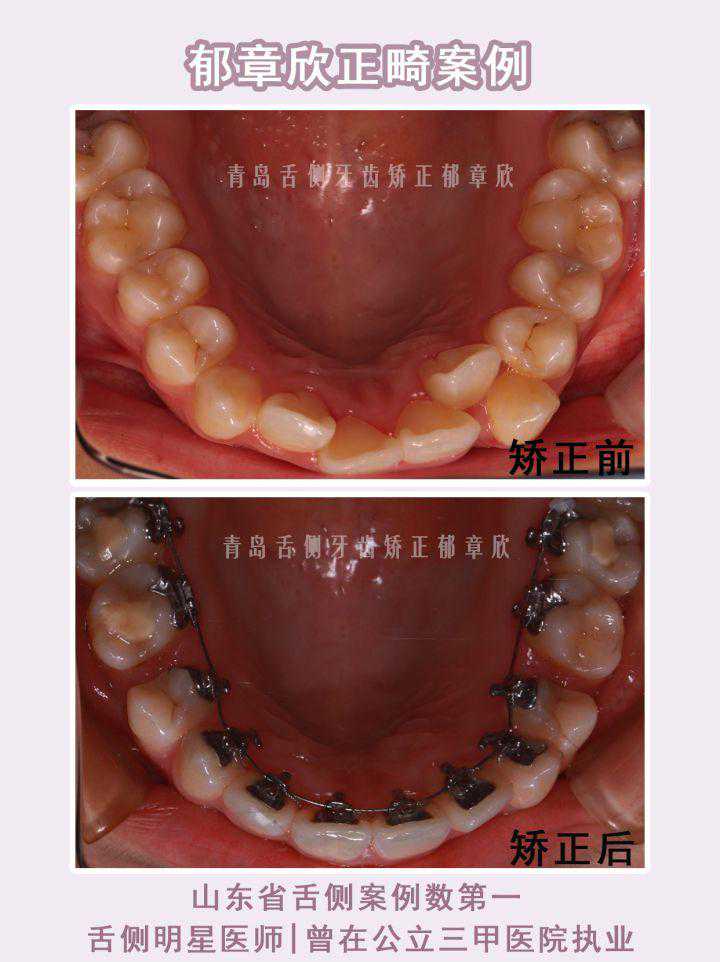

案例一:【舌侧案例分享|牙齿不齐+笑线不调】

患者因牙列不齐,笑容不好看想要通过正畸改善。

姑娘的父亲有很多朋友是牙科医生,在找到我面诊前,是看了很多的牙科医生,最后了解到我擅长做舌侧矫正,自己也意向做舌侧矫正,就特意从潍坊来找到我进行面诊。在面诊沟通中,她对我的方案设计也很认可满意,最后就决定在我这正畸了。

矫正前她的牙列不齐,特别是上牙列虎牙异位,也导致她的笑弧笑线与下唇不平行,笑起来自然不太好看。此外,她笑露牙龈过多,有露龈笑,也影响了笑容美观。

目前仍在矫正中,牙列排齐和笑线的设计,可以看到她牙齿已初步排齐,也有自然笑弧,笑容好看了不少。接下来还会继续调整露龈量和牙齿咬合关系,结果还能更好。